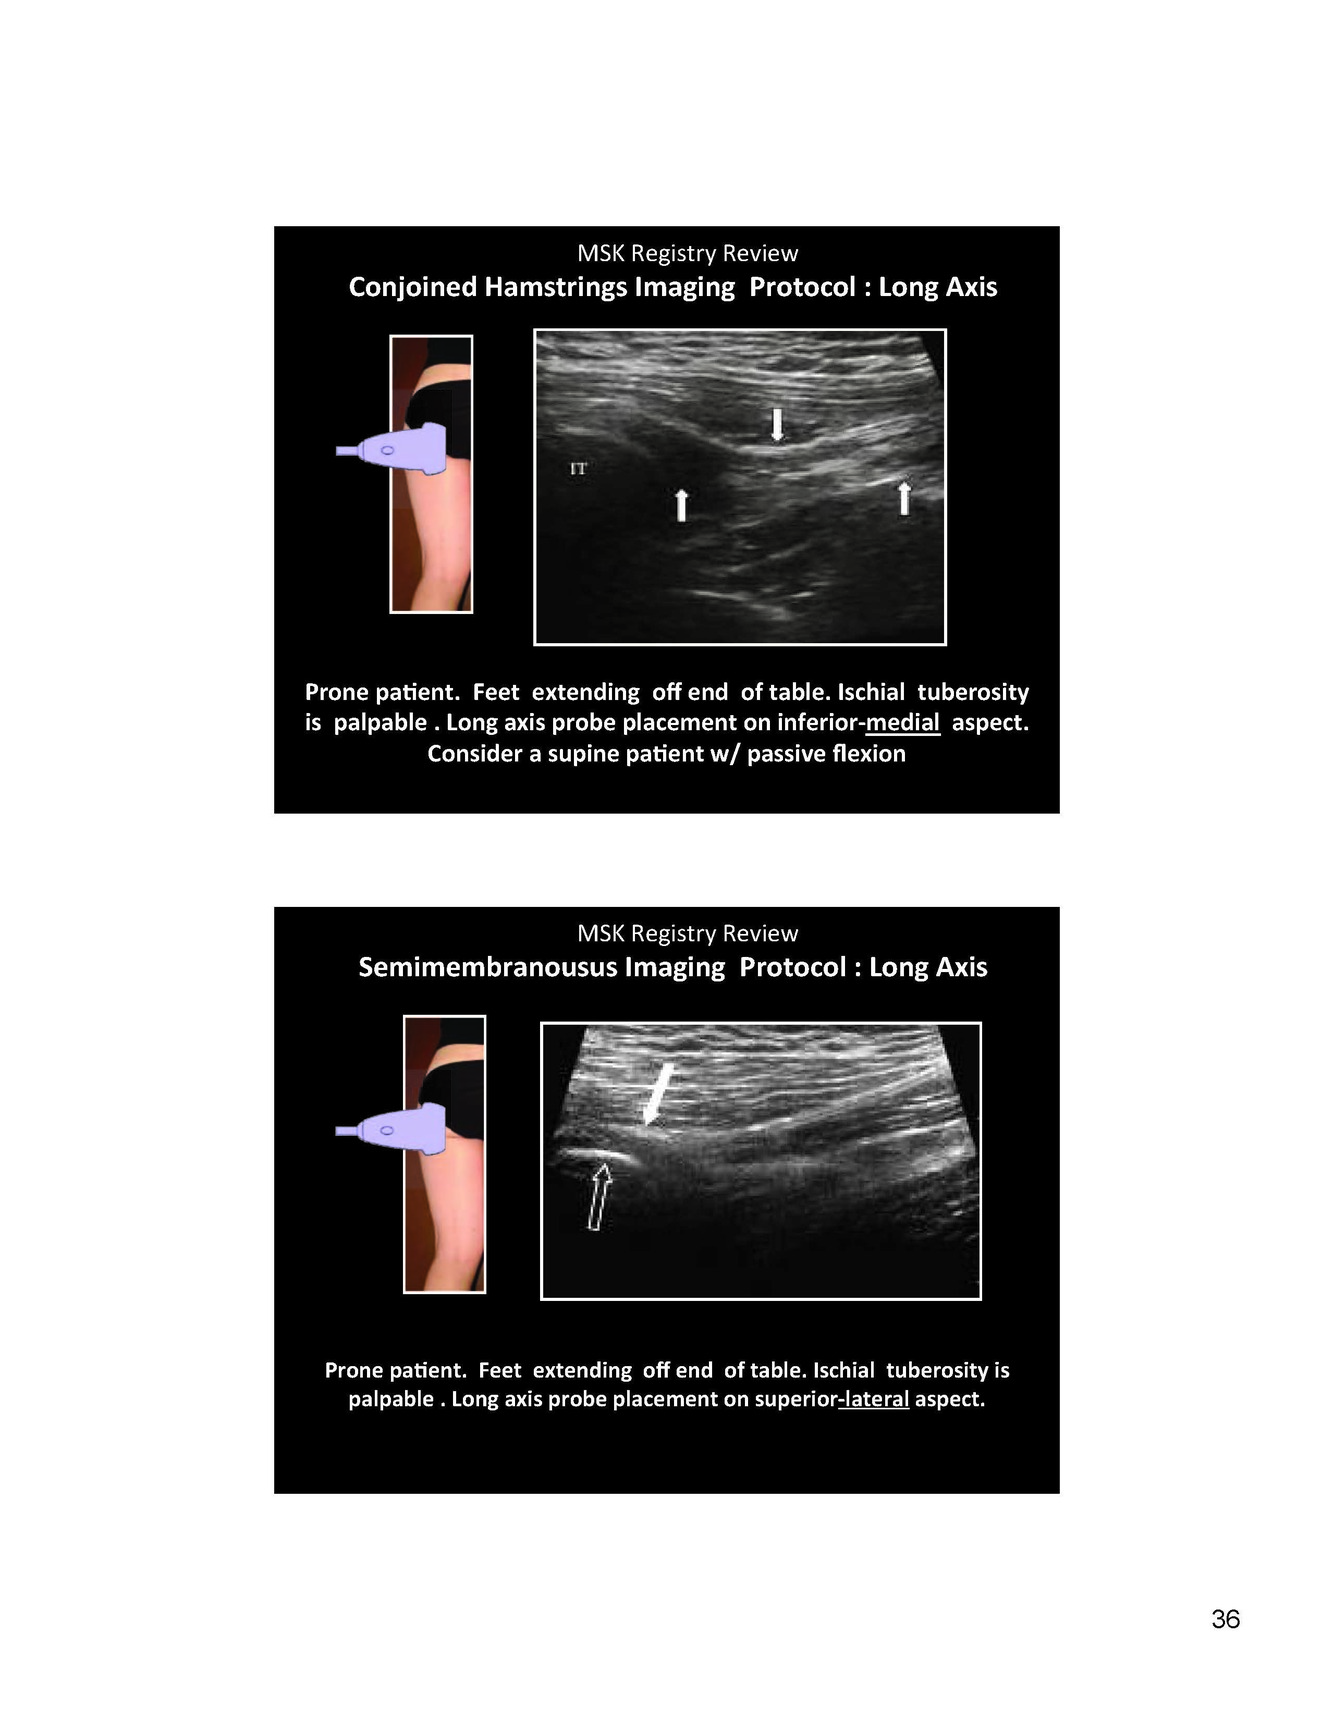

Image of femoral nerve sonograph

Not nerve to FA

The LCFM is visualized between 2 hyperechoic fascial layers

Fascia lata superficial sheath of thigh and fascia liaca covering iliacus and psoas